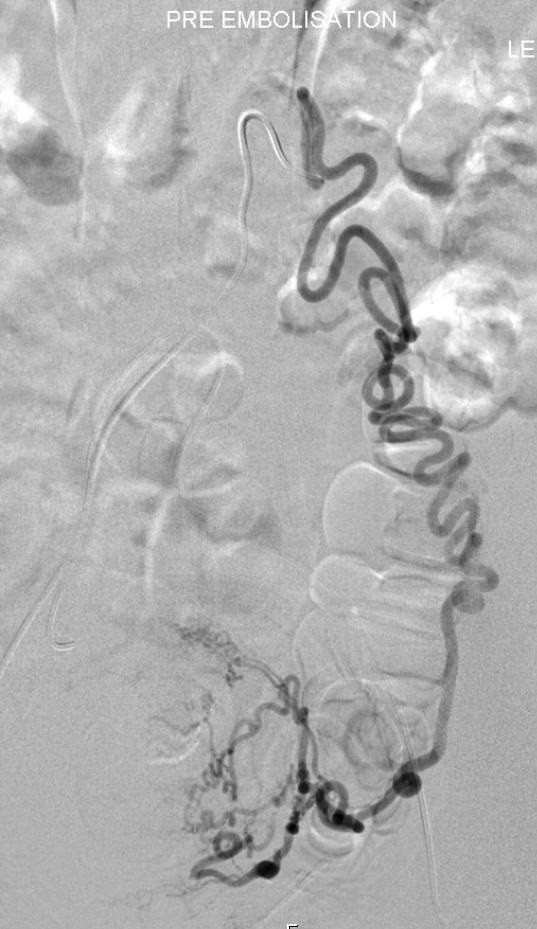

技术上的考虑:用标准的微粒缓慢栓塞,当肌瘤周围造影剂染色和子宫动脉内抗压增高时,增加栓塞颗粒的大小(700~900或900~1000)以避免非靶器官的卵巢实质栓塞(Kim et al JVIR 2008, 19:195-200)。

| 调整栓塞剂的注射速率,使血流离开卵巢 |

II 型 子宫- 卵巢动脉吻合时,卵巢动脉直接供应肌瘤

| II 型卵巢动脉-子宫动脉吻合(U-O anastomosis) |